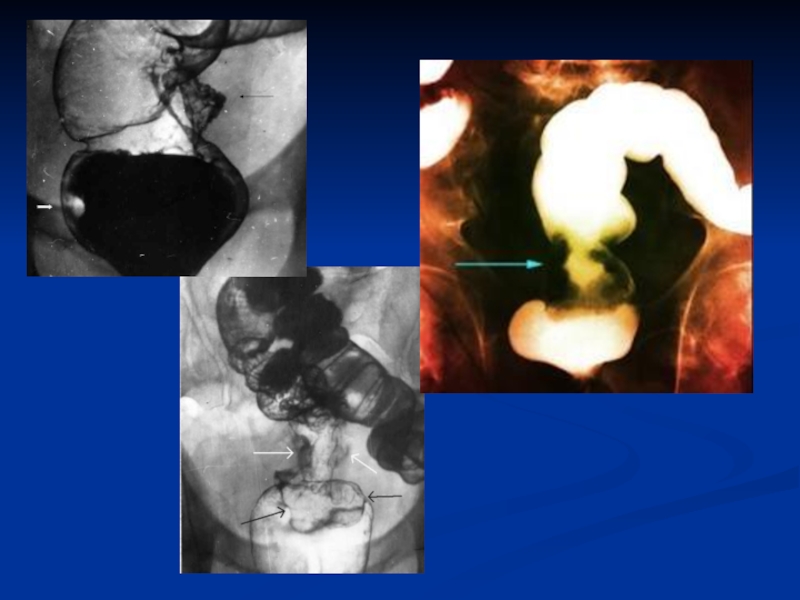

Слайд 23 Ирригоскопия

Ирригоскопия

Слайд 24Ирригоскопия